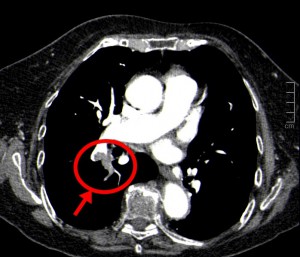

Caso 41

El angio-TC de arterias pulmona rerevela una trombosis en arterias pulmonares que afectan a diversas arterias del LSD. También hallamos bronquiectasia retráctil del LSD. No se observan nódulos ni infiltrados pulmonares. No hay tampoco derrame pleural ni infartos pulmonares.